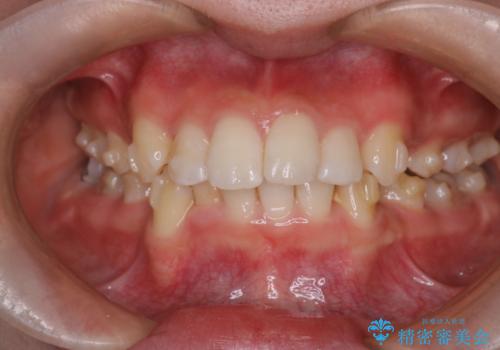

- 前歯から奥歯にかけて歯の重なりが激しい歯のがたつき(重度叢生)を主訴にご来院されました。精密検査の結果、歯が並ぶスペースが大幅に不足しており、歯並びを整え、口元を美しく引っ込めるためには、スペースの確保が必要と診断しました。そこで、上下左右の第一小臼歯(4番目の歯)を計4本抜歯し、そのスペースを利用して歯並び全体を整える抜歯矯正の治療計画を立案。装置には、透明で目立たないインビザラインを採用し、審美性と治療効果の両立を目指しました。

今回の治療では、重度の叢生を改善するため、まず計画通り上下左右4本の小臼歯を抜歯し、歯を並べるための十分なスペースを確保しました。装置には透明で取り外し可能なインビザラインを使用。抜歯によってできたスペースを最大限に活用し、マウスピースを定期的に交換しながら、デコボコを解消しつつ、前歯を効果的に後退させました。

治療の結果、長年の悩みであった重度の歯のがたつきが解消され、口元の突出感も改善。機能的にも安定し、審美的にも美しい、理想的な歯並びを獲得していただけました。